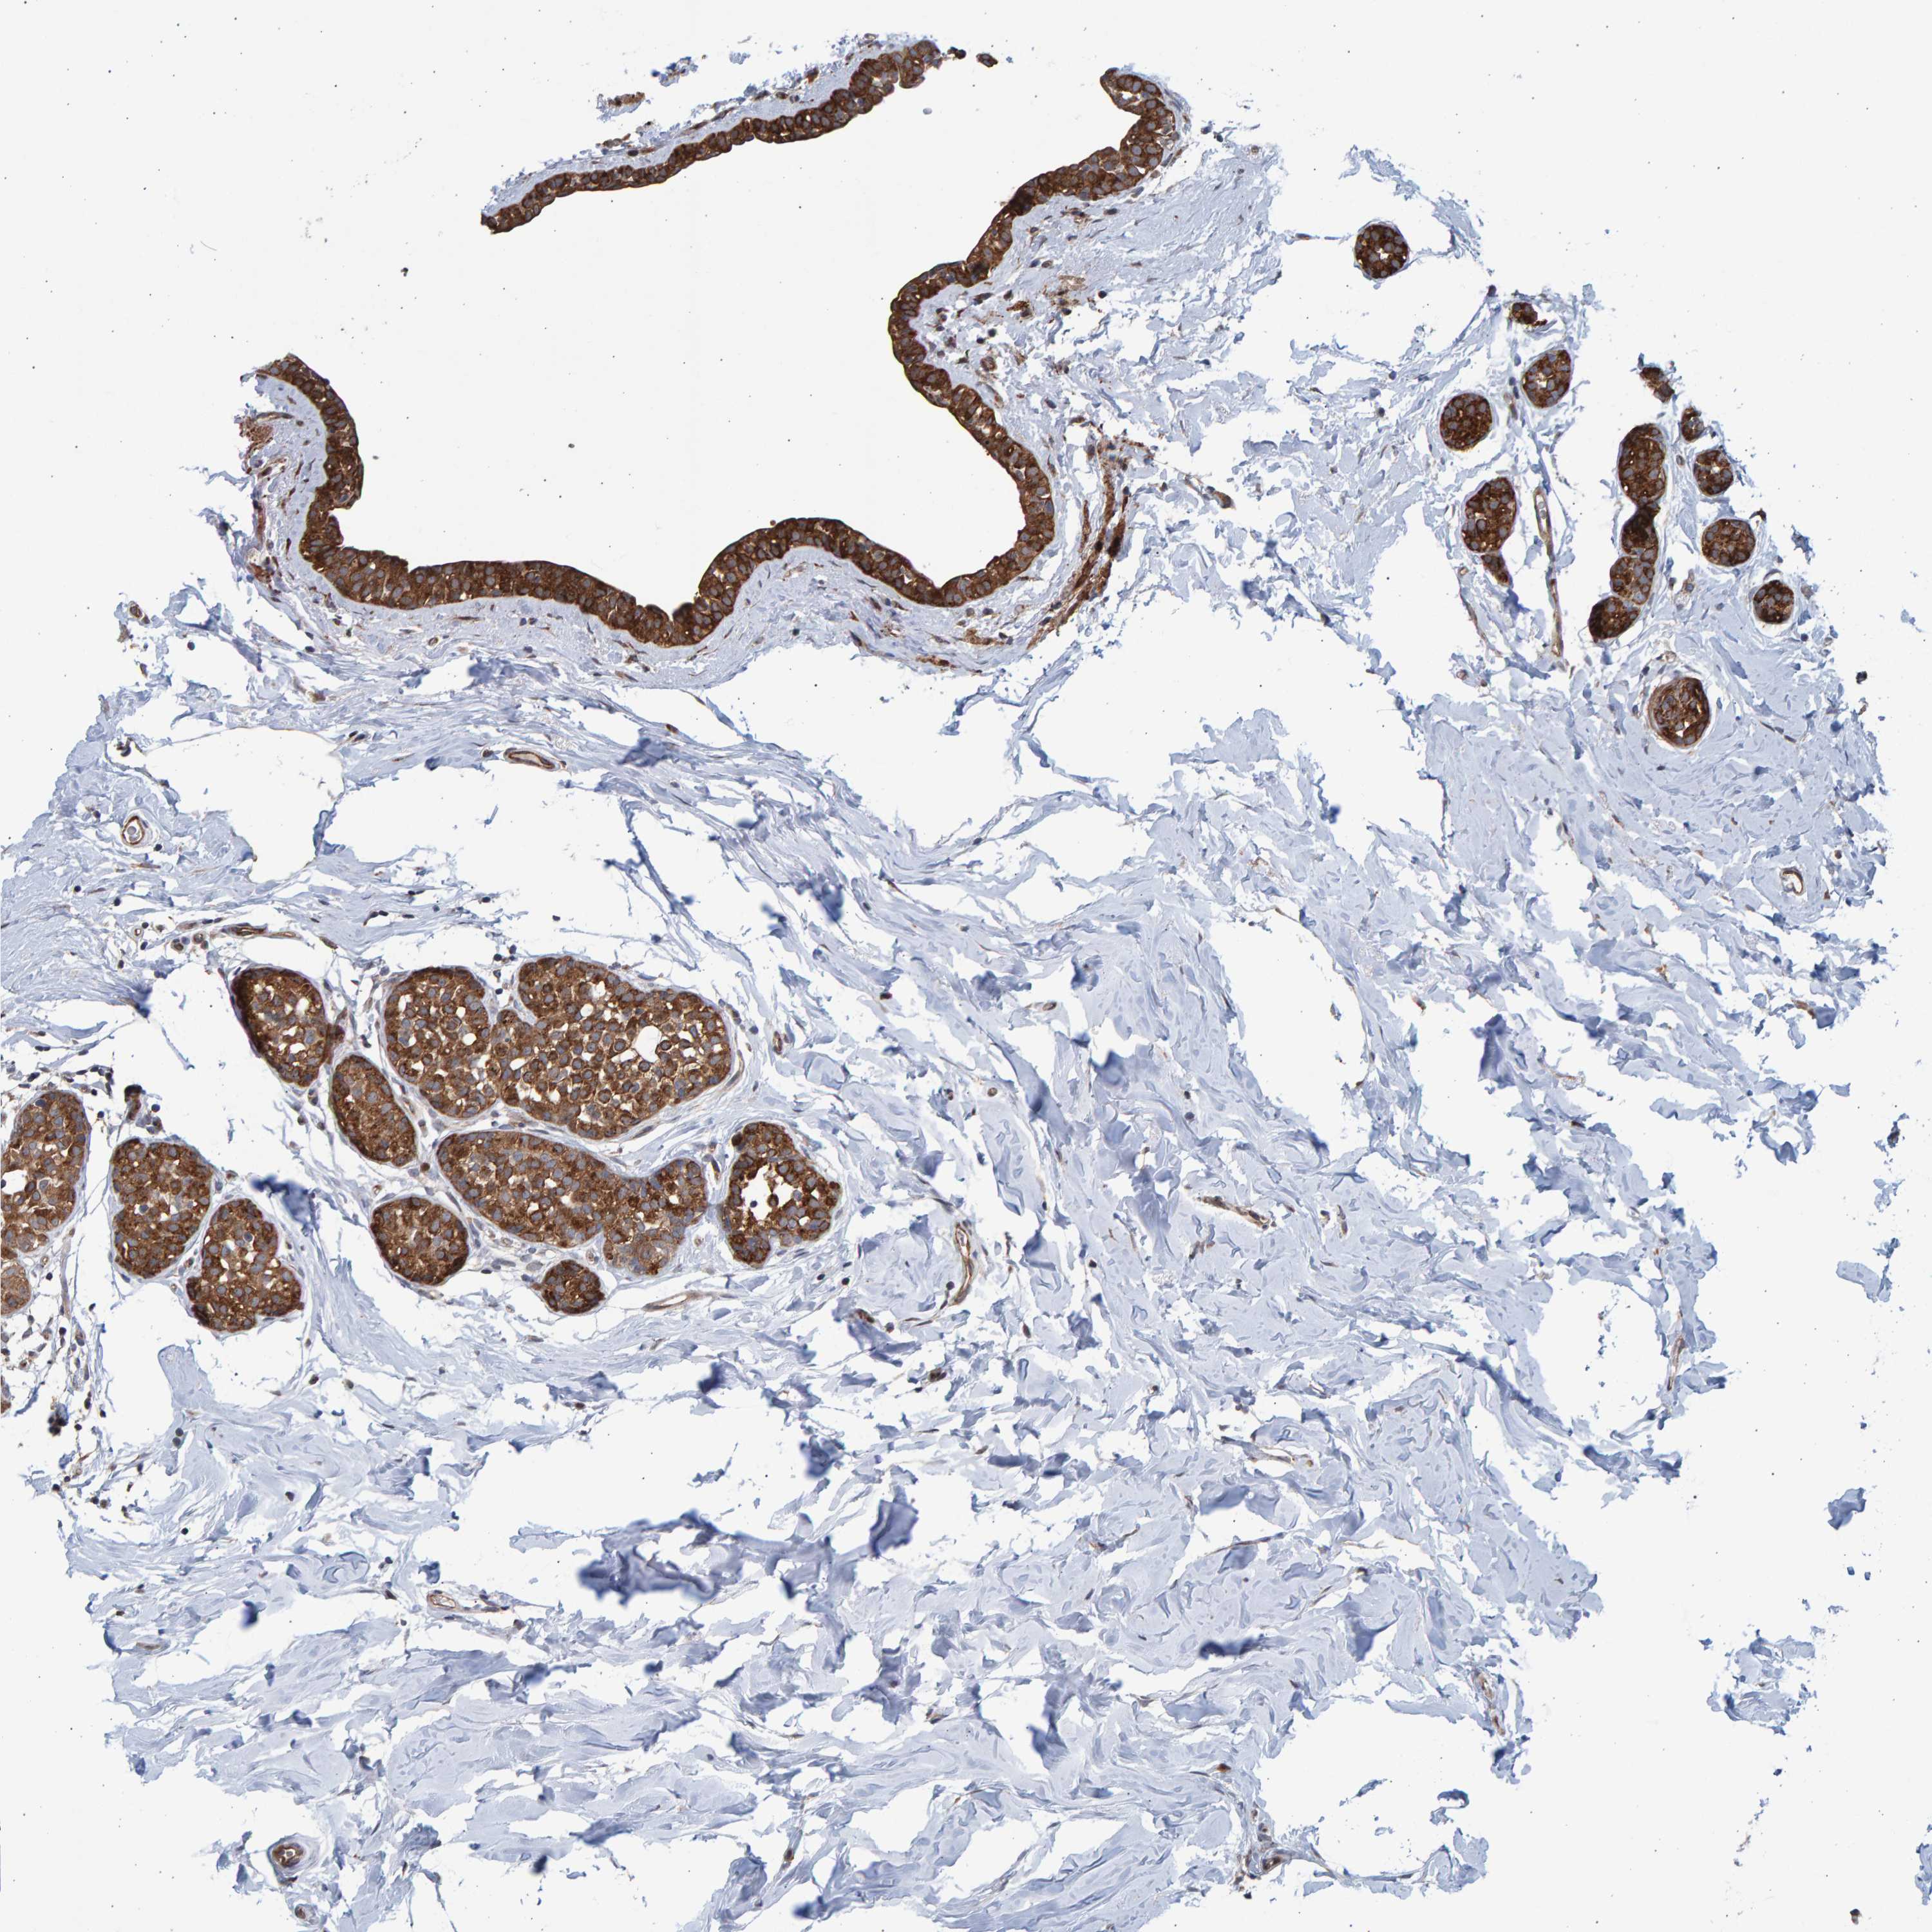

CANCER BREAST CANCER Show tissue menu

BRCA TCGA BRCA VALIDATION PROTEIN EXPRESSION